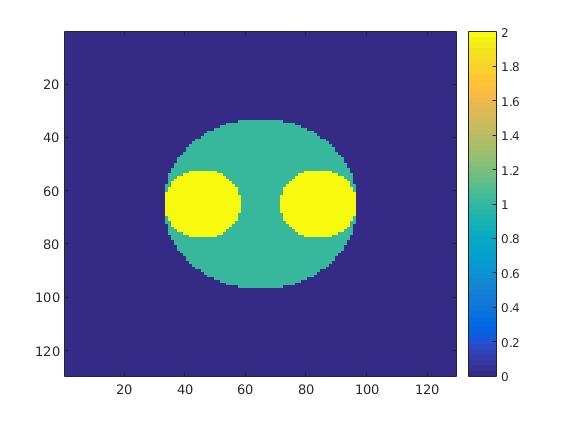

5.2 Monte Carlo Simulation

In order to test the behaviour of the proposed method in a more realistic, random-based test case, we performed a Monte Carlo simulation for dynamic SPECT imaging. First, we created a simple image phantom consisting of an outer and two inner circles which represents the structure of the region of interest (see figure 8(a)). Within those regions we assumed concentration curves over a time period of 90 time steps as displayed in figure 8(b). Based on the tracer intensity in an image frame at each time step, we created a variable number of random decay events (where the number is proportional to the average concentration in one pixel in the whole image frame per time step) with a probability proportional to the concentration in every subregion. They are detected by a virtual double head gamma camera rotating around the patient by 46 degrees per time step, which consists of 374 detector bins. Every simulated decay event is projected onto the scanner and counted by the corresponding detector bin.

In two different tests we fixed the number of events counted by the detector equal to (resp. ) times the average concentration in one pixel. The resulting sinogram images of the accumulated counts in each bin are shown in figure 9.